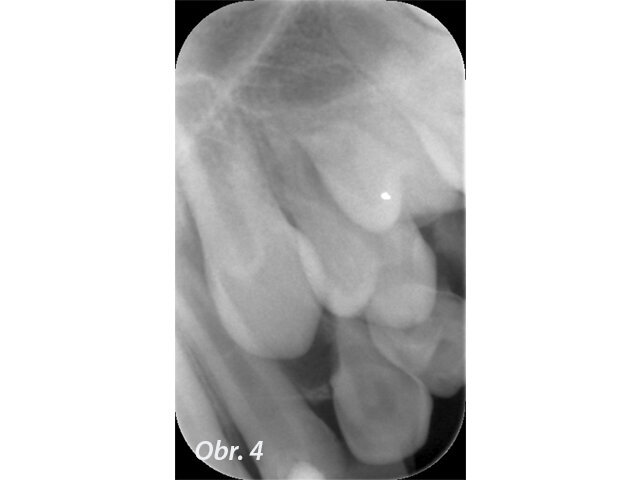

Prvním možným řešením je umístění MTA přímo do dekontaminovaného apexu zubu. U kratších rovných kořenů jde se správným instrumentáriem o poměrně snadný výkon. V případě 12letého chlapce referovaného po fraktuře zubu šlo ale o postranní řezák 12 s výrazným apikálním zahnutím, kam bylo s rigidní zahnutou koncovkou tzv. „MTA gun“ v roce 2011 nemožné aplikovat dostatečně hluboko. V dnešní době s flexibilními koncovkami MAP systému by zřejmě tento problém neexistoval. Přestože nebyl zub zcela zaplněn, předchozí dekontaminace a potentní dětská tkáň zajistily, že se veškerý zbývající prostor kořene vyplnil zřejmě dentinoidní tkání. Zub byl opatřen adhezivní dostavbou s FRC čepem a pryskyřičnou korunkou. (Obr. 1–3)

Popsané řešení má výbornou prognózu.